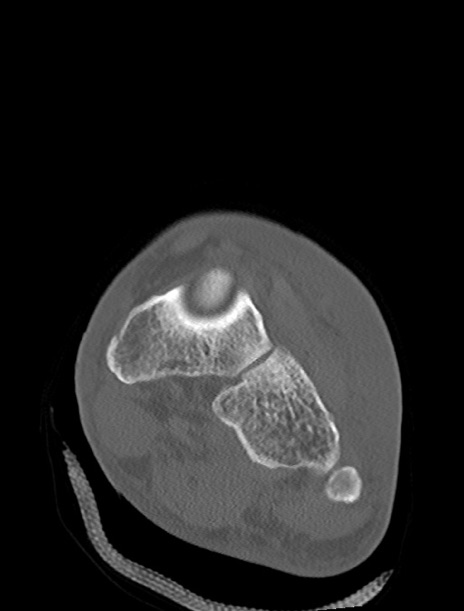

症例37 左足関節CT(冠状断像)

左足関節CT

横断像